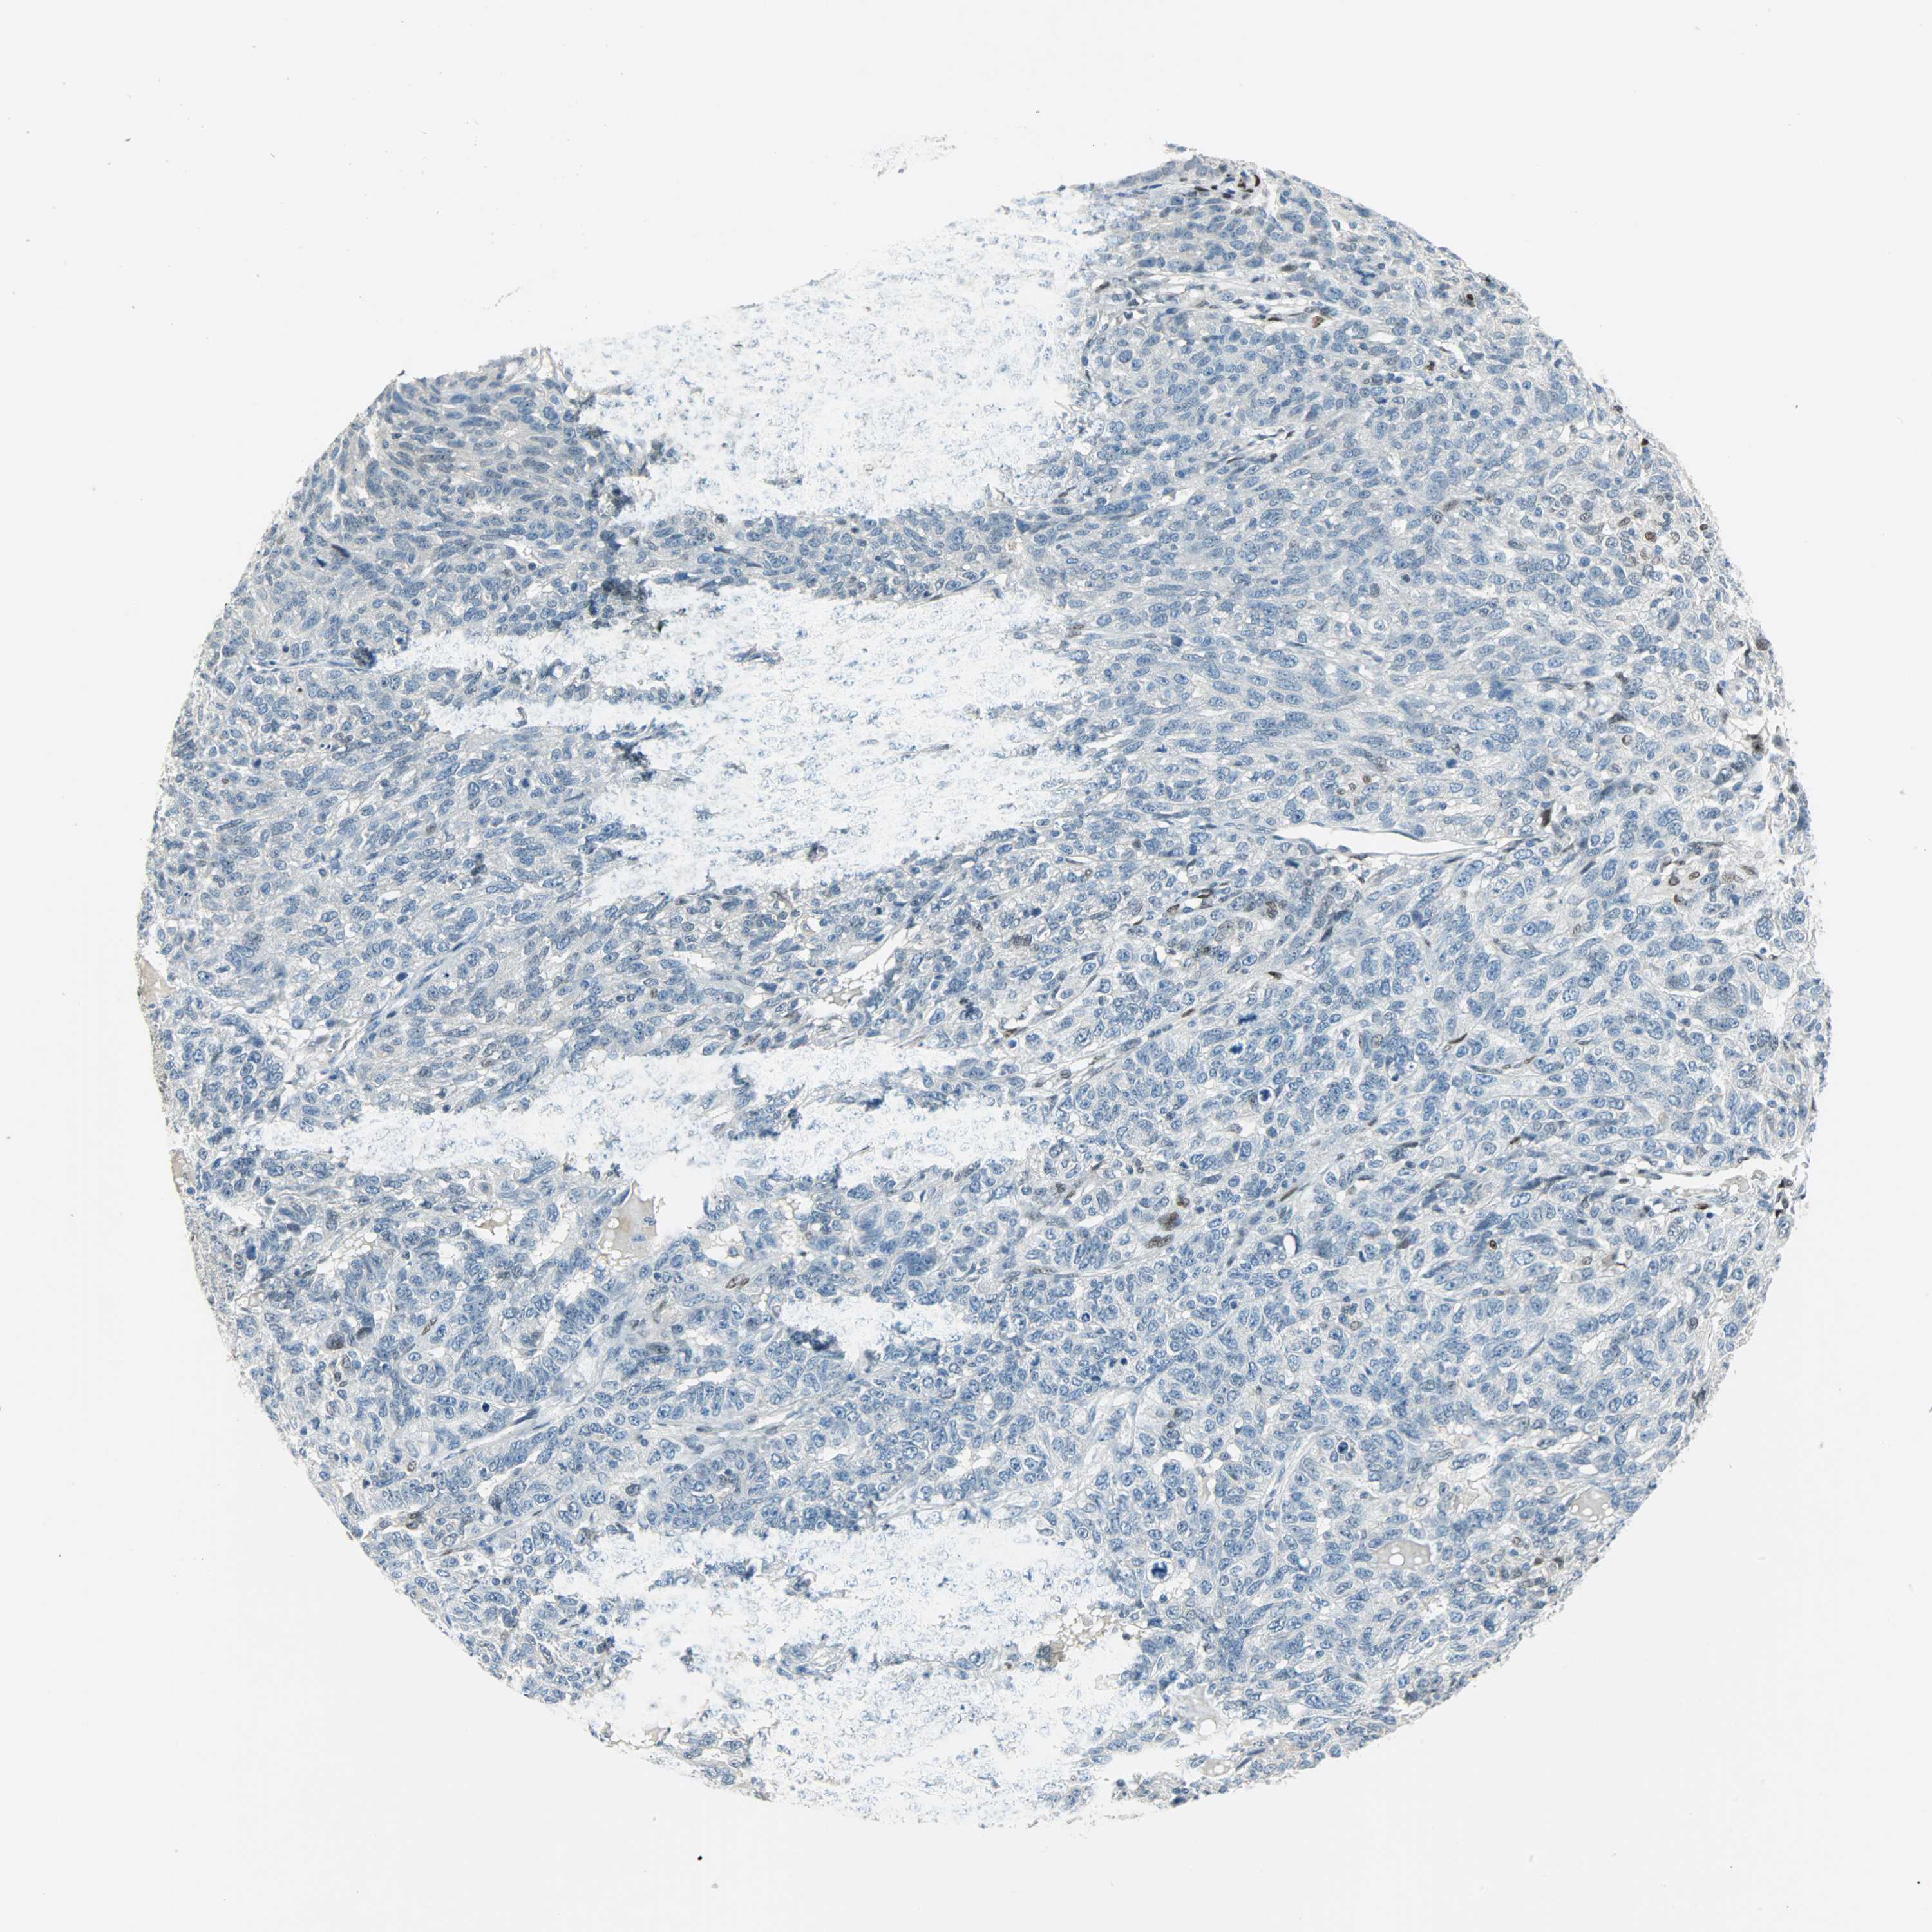

OVARIAN CANCER - Protein expressioni

A mouse-over function shows sample information and annotation data. Click on an image to view it in a full screen mode. Samples can be filtered based on level of antibody staining by selecting one or several of the following categories: high, medium, low and not detected. The assay and annotation is described here.

Note that samples used for immunohistochemistry by the Human Protein Atlas do not correspond to samples in the TCGA dataset.

Antibody stainingi

Antibody staining in the annotated cell types in the current human tissue is reported as not detected, low, medium, or high, based on conventional immunohistochemistry profiling in selected tissues. This score is based on the combination of the staining intensity and fraction of stained cells.

Each image is clickable and will lead to virtual microscopy that enables deeper exploration of all samples and also displays staining intensity scores, fraction scores and subcellular localization as well as patient and tissue information for each sample.

Antibody HPA019149

Antibody CAB004464

Staining

High

Medium

Low

Not detected

Intensity

Strong

Moderate

Weak

Negative

Quantity

>75%

75%-25%

<25%

None

Location

Nuclear

Cytoplasmic/membranous

Cytoplasmic/membranous,nuclear

Cystadenocarcinoma, serous, NOS

Carcinoma, endometroid

Cystadenocarcinoma, mucinous, NOS

Carcinoma, NOS